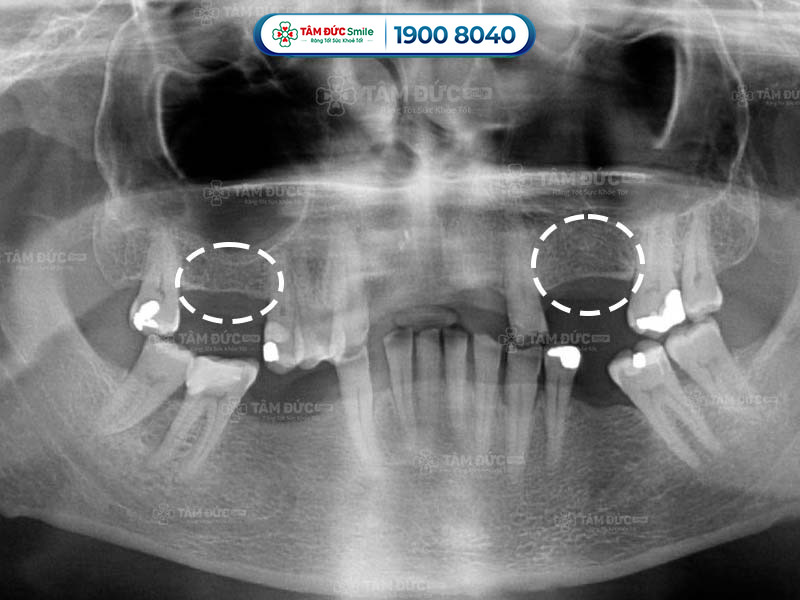

1.1. Quan sát dấu hiệu tiêu xương răng qua phim chụp X-Quang

Một trong những dấu hiệu tiêu xương răng rõ ràng nhất là hiện tượng hạ thấp của sàn xoang hàm. Sàn xoang hàm là một vách ngăn mỏng nằm giữa xoang hàm và xương ổ răng. Khi răng bị mất, lực nhai không còn tác động lên vùng xương ổ răng, làm cho xương ổ răng teo dần.

Trên phim chụp X-Quang, bác sĩ dễ dàng nhận thấy sự hạ thấp của sàn xoang hàm. Sự hạ thấp này được đánh giá bằng cách đo khoảng cách từ sàn xoang đến nướu răng.

Dấu hiệu tiêu xương răng qua phim X-Quang